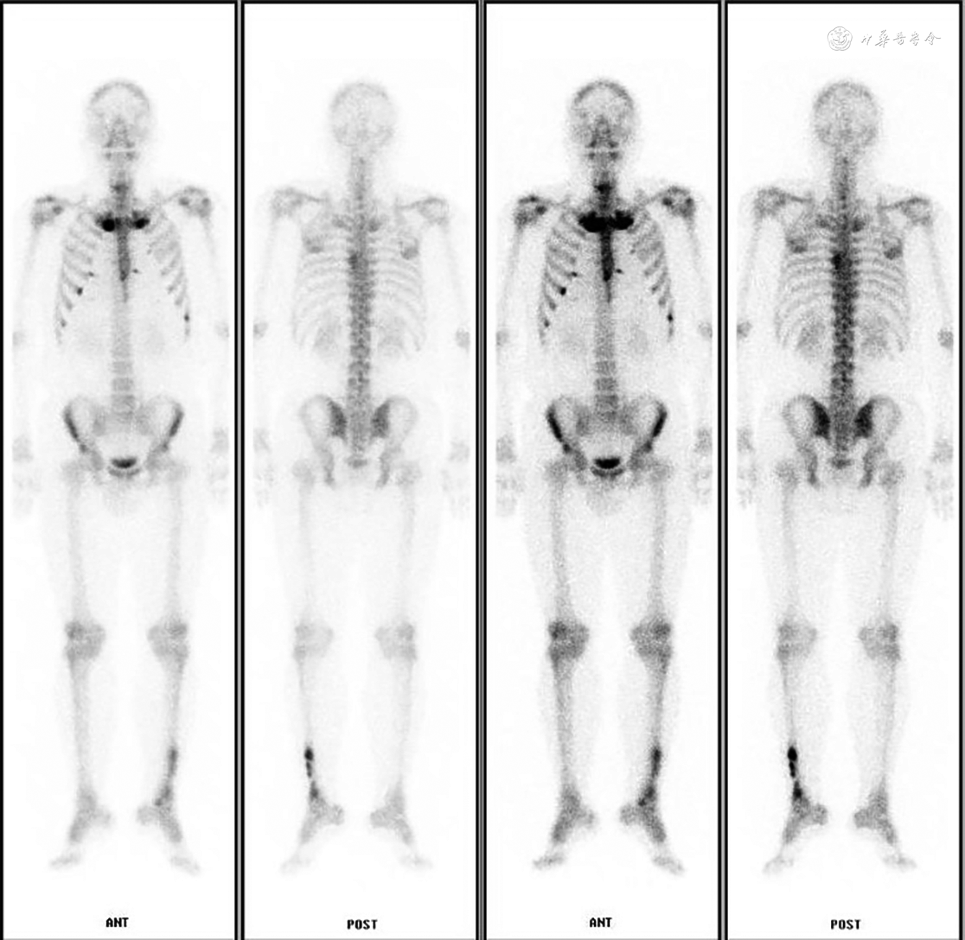

患者男,40岁,因“反复咽痛30年,双手足皮疹伴关节疼痛4年”就诊于北京大学第三医院耳鼻咽喉头颈外科。患者30年来反复发作咽痛,每年5~6次,每次发作诊断“急性扁桃体炎”,服用头孢类抗生素后可缓解,4年前出现间断双手掌、双足底脓疱疹,诊断“掌跖脓疱病?”,予米诺环素胶囊口服,环吡酮胺、卤米松乳膏外用,症状仍反复。2年前出现胸锁关节、双肩、髋关节疼痛,诊断“滑膜炎-痤疮-脓疱病-骨质增生-骨炎(synovitis-acne-pustulosis-hyperostosis- osteitis,SAPHO)综合征”,予塞来昔布胶囊治疗,效果欠佳。建议联合应用肿瘤坏死因子α(TNF-α)靶向药物治疗,患者拒绝。患者自觉咽痛发作与皮疹、关节疼痛发作无明显相关。既往长期吸烟史、左侧胫骨骨折术后。母亲患类风湿性关节炎。查体见双手掌少量红斑、脱屑,胸锁关节肿大、无触痛,左侧扁桃体Ⅱ度、右侧扁桃体Ⅰ度,未见充血,隐窝洁。实验室检查:红细胞沉降率(erythrocyte sedimentation rate,ESR)、C反应蛋白(C-reactive protein,CRP)升高,抗SS-A52抗体弱阳性,总T细胞绝对数升高,白介素(IL)-17、干扰素(IFN)-γ降低,IL-6、TNF-α升高,抗链球菌溶血素“O”(antistreptolysin O,ASO)、类风湿因子(rheumatoid factor,RF)、抗核抗体(antinuclear antibody,ANA)、人白细胞抗原(Human Leukocyte Antigen,HLA)-B27阴性。全身骨显像示“双侧胸锁关节、双肩关节、双侧多发肋骨软骨连接处、左侧第7胸肋关节符合SAPHO表现”(图1)。入院诊断为“慢性扁桃体炎;SAPHO综合征”,住院后在全身麻醉下行扁桃体切除手术,术后予二代头孢类抗感染治疗1周。患者术后1个月随访,诉掌跖脓疱消退,胸锁关节、双肩、双髋关节疼痛较前明显减轻,查体未见双手掌、足底皮疹。

本例患者为40岁男性,主要表现为掌跖脓疱,胸锁关节及双肩、髋关节疼痛,CRP、血沉、TNF-α升高,ANA阴性,抗SS-A52抗体弱阳性,结合全身骨显像“牛头征”,符合SAPHO表现;患者无严重痤疮表现,IL-17降低,与典型SAPHO表现较不符。该患者经皮肤科及风湿免疫科药物治疗后症状仍反复,且依从性较差。既往合并慢性扁桃体炎及吸烟史。入院后行扁桃体切除手术及术后1周抗生素治疗后,皮损及关节症状较前明显减轻,且抗生素停药后症状未反复。因此,我们推测扁桃体切除术为症状改善的主要原因。患者症状改善可能与局部感染灶消除、机体内异常T细胞介导免疫反应减少相关。本例患者仍有待长期随访,重点关注临床症状有无复发,化验指标是否转阴,术后全身骨显像有无变化。